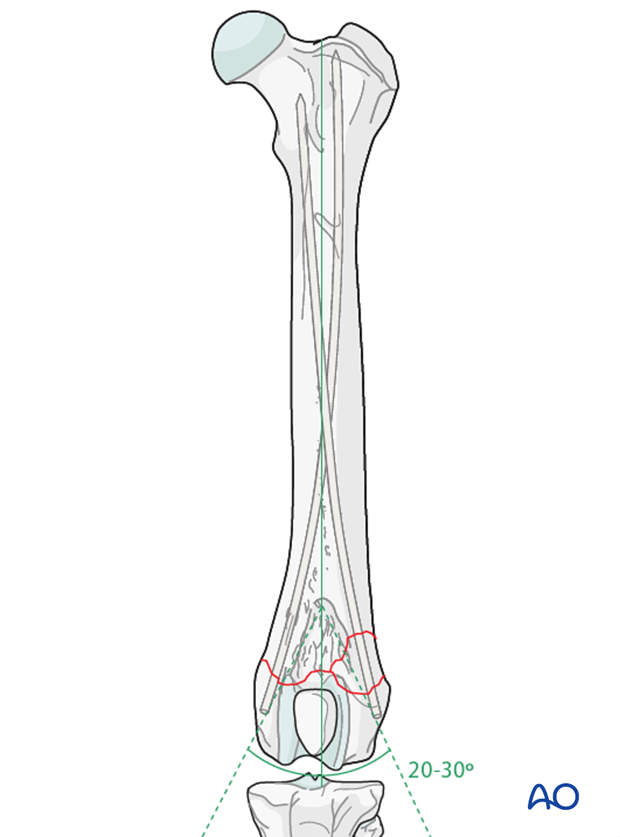

Alternatively, the pins may be inserted using a modified Rush/dynamic cross pinning technique. In this case, the pin insertion sites are the same, except each pin is angled 20-30 degrees to the long axis of the femur. A slightly smaller diameter pin is used to achieve success with this technique.

With the modified Rush/Dynamic cross pinning technique, the pins do not penetrate the cortex of the femoral diaphysis but create friction by bending and creating a “spring like” action against the endosteum.

Due to the anatomical differences between the canine and feline femur, this technique is easier to perform in the cat, as there is less caudal curvature in the distal femur.

As the pins are advanced they bounce off the endosteal cortex and slide up the medullary canal. Advancement of the pins stop when they reach the proximal metaphysis.